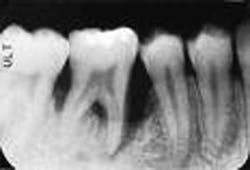

We didn't get the grant; so, ultimately, we had to drop the project. But Tom's preliminary research was fascinating. He showed that the cavitation did indeed occur around an ultrasonic tip, but that its pattern varied dramatically depending on tip design, oscillation frequency, and power setting (see Figure 4). This suggested that the effectiveness might be improved significantly to optimize delivery of medicaments.